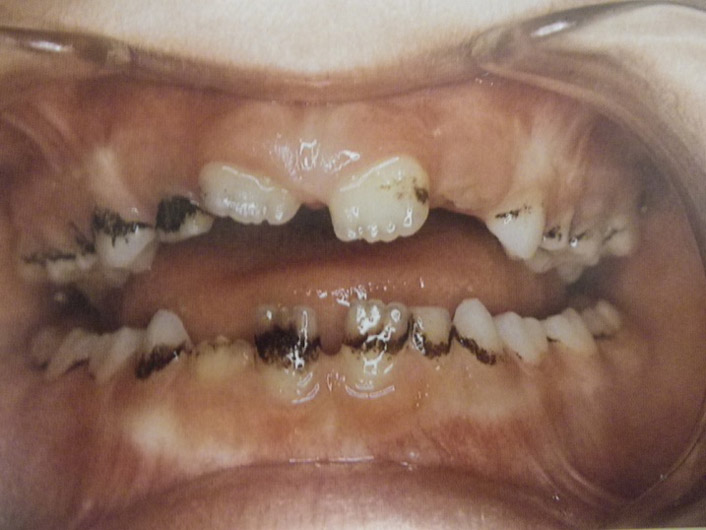

Υπενασβετίωση της αδαμαντίνης

Συνήθως εκδηλώνεται με λευκές, κίτρινες ή καφέ κηλίδες στους τομείς και τους γομφίους, μπορεί όμως να επηρεάσει και άλλα δόντια. Η κλινική εικόνα μπορεί να περιορίζεται μόνο στην εμφάνιση αυτών των κηλίδων, ή να είναι πιο σοβαρή προκαλώντας απώλεια της αδαμαντίνης του δοντιού, με συνέπεια την εμφάνιση ευαισθησίας και πόνου καθώς και τερηδόνας.

Η κατάσταση αυτή της αδαμαντίνης οφείλεται σε διαταραχή της διάπλασής της με αποτέλεσμα την ελλιπή ενσωμάτωση των μετάλλων στη δομή της. Έχουν ενοχοποιηθεί διάφοροι παράγοντες (περιβαλλοντικοί, ασθένειες της μητέρας και του βρέφους, διατροφή κ.ά.) οι οποίοι μπορούν να προκαλέσουν αυτές τις διαταραχές.